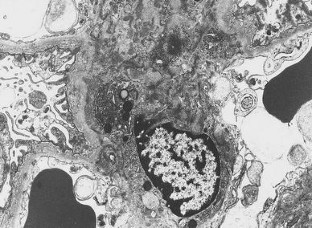

We describe a 24-year-old woman with a distinctive glomerular lesion. She presented with nephrotic syndrome and the diagnosis of systemic lupus erythematosus was made on the basis of laboratory and clinical findings. Renal biopsy showed a bubbling appearance of the glomerular capillary wall indicating lupus nephritis class V. On an electron microscopy, the glomerular basement membrane (GBM) was irregularly thickened and contained abundant vesicular and microtubular bodies. In addition, there were many epithelial foot processes infolding into the GBM. A few small deposits were observed beneath the foot processes and around the vesicular and microtubular bodies. Although the clinicopathological significance of podocytic infolding has not been fully elucidated, it may be a novel morphological entity in the glomerulonephritides.

Fig. 1